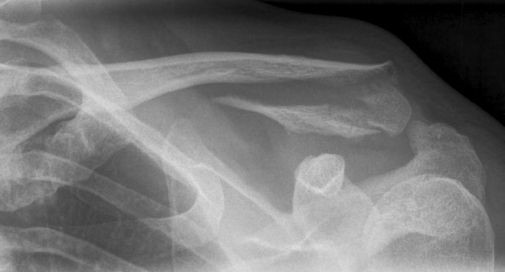

De sleutelbeenbreuk

De sleutelbeenbreuk is één van de meest voorkomende botbreuken. Het is (gelukkig) bijna altijd een gemakkelijk genezende botbreuk. Er doen zich zelden complicaties voor. De behandeling is eenvoudig; enige weken rust is vaak alles wat nodig is.

Omdat het sleutelbeen door zijn ligging zo makkelijk is te onderzoeken, kan de arts na zijn onderzoek meestal met zekerheid vaststellen of uw sleutelbeen gebroken is. Vaak zal de arts er voor kiezen aanvullend een röntgenfoto te maken.